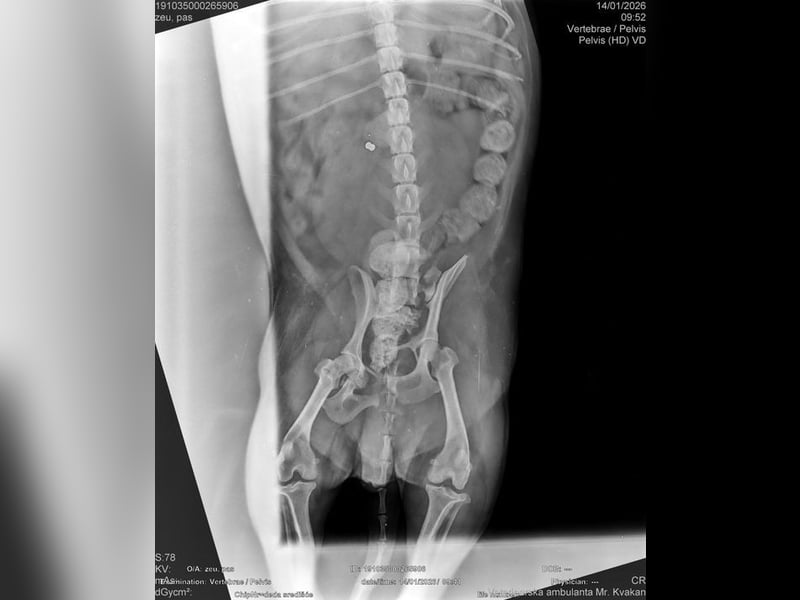

Die medizinische Untersuchung ergab, dass außer einem Schrecken, keine Verletzungen festzustellen waren. Auch die Röntgenaufnahmen bestätigten diese Diagnose.